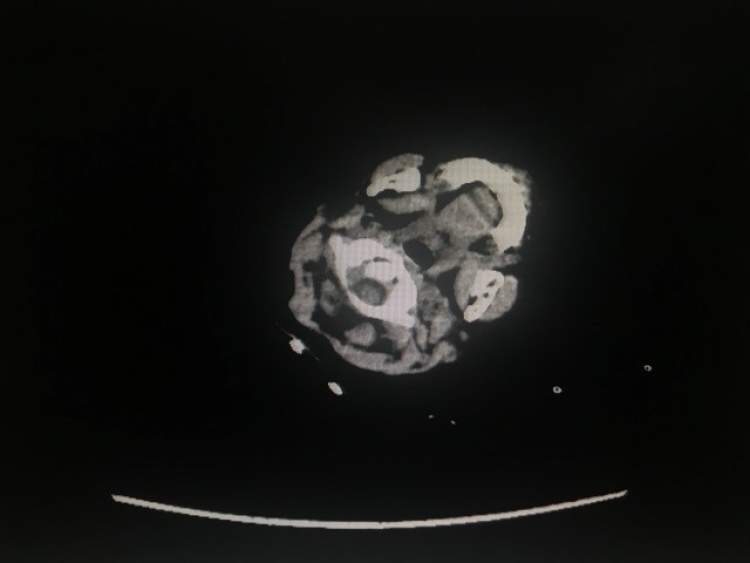

2018年11月底,小欣来到上海儿童医学中心神经外科就诊,经核磁共振提示下丘脑占位,诊断为下丘脑错构瘤。

在完善各项术前检查后,小欣接受了错构瘤切除术治疗。以梁秦川、杨波医生为主刀的神经外科团队在全麻下行前纵裂胼胝体穹隆间入路下丘脑错构瘤切除术。

手术中,医生们发现小欣的左侧下丘脑肿瘤约有1×1.5cm大小,将肿瘤次全切除,创面彻底止血,生理盐水反复冲洗清亮后,缝合硬膜,手术进行近5小时顺利结束。